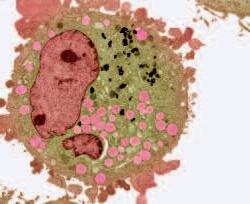

La pagina a fianco mostra l'immagine di una cellula tumorale reale, visualizzata al microscopio elettronico, che ingrandisce questa cellula 6500 volte rispetto alle sue normali dimensioni. Questo tipo di cellula prende il nome di carcinoma, cioè derivante da cellule epiteliali, il tipo di cellule che rivestono sia le superfici interne (polmoni, intestini) che esterne (pelle) del corpo.

Grazie a questo ingrandimento si possono identificare chiaramente alcune delle caratteristiche di tutte le cellule tumorali: a) l'enorme nucleo cellulare dalla forma insolita che spiega la loro grande capacità di riprodursi e b) la struttura non uniforme, complessa della superficie cellulare, che riflette una forte attività di secrezione di sostanze prodotte dalle cellule tumorali.

Una delle più importanti molecole secrete dalle cellule tumorali in grandi quantità sono gli enzimi a ‘forbice’ che digeriscono il collagene. Sono aggiunti graficamente a questa immagine, sotto forma di strutture simili ad un ‘pacman’ rosso.

Naturalmente questi sfere, nella vita reale, sono molecole biologiche, proteine, che hanno la capacità di tagliare le fibre di collagene e di altre molecole del tessuto connettivo. L‘immagine sopra mostra che non c’è un solo tipo di 'pacman' ovvero di queste molecole, ma

Digestione del tessut o connet tivo del tessuto connetti vo diversi tipi, quali il plasminogeno/plasmina e le metalloproteasi (strutture colorate tridimensionali). Queste molecole migliorano il loro effetto distruttivo attivandosi reciprocamente in forma di reazione a catena in cascata.